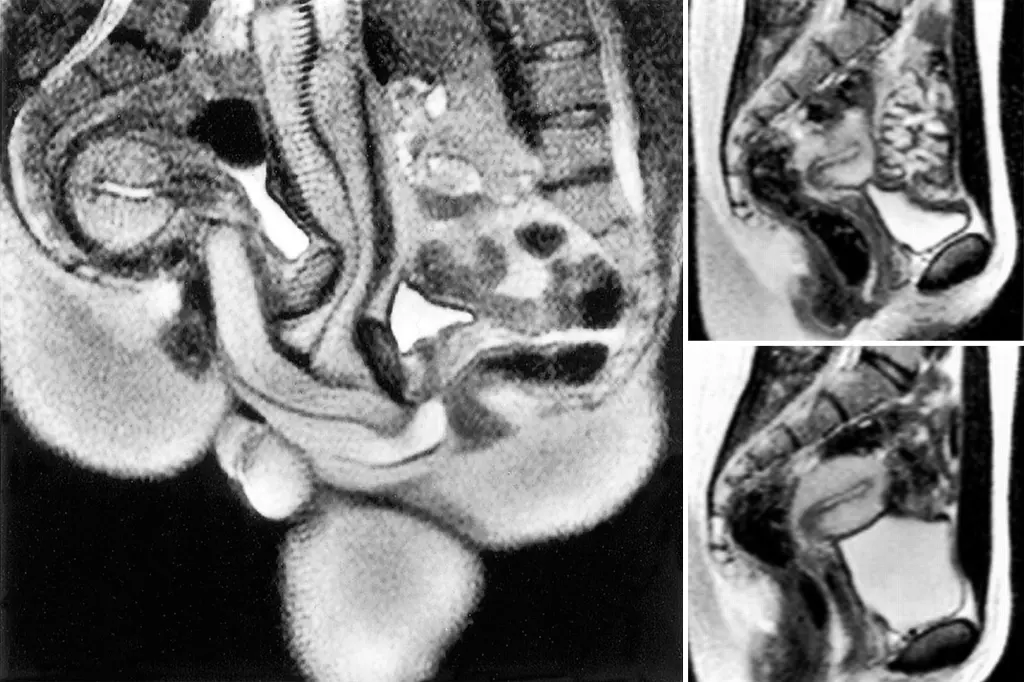

എം.ആർ.ഐ മെഷീനുകൾ ആദ്യമായി ഉപയോഗിച്ചു തുടങ്ങിയ കാലമായിരുന്നു അത്. അതുകൊണ്ടുതന്നെ വ്യക്തമായ ചിത്രങ്ങൾ ലഭിക്കാൻ ഏറെ സമയമെടുത്തിരുന്നു. കൺട്രോൾ റൂമിൽ നിന്നും നിർദ്ദേശം ലഭിക്കുന്നതുവരെ ചിലപ്പോൾ മിനിറ്റുകളോളം ഒരേ പൊസിഷനിൽ തന്നെ ദമ്പതികൾക്ക് തുടരേണ്ടി വന്നിട്ടുണ്ട്. വളരെ ഇടുങ്ങിയ, വെറും 50 സെന്റീമീറ്റർ മാത്രം വ്യാസമുള്ള ആ ട്യൂബിനുള്ളിൽ സാധാരണ ഗതിയിലുള്ള (missionary) പൊസിഷനുകൾ സാധ്യമായിരുന്നില്ല. അതിനാൽ വശങ്ങളിലേക്ക് ചരിഞ്ഞുകിടന്നുള്ള (spooning) രീതിയാണ് ഇവർ തിരഞ്ഞെടുത്തത്.

ലോകത്തെ അമ്പരപ്പിച്ച കണ്ടെത്തലുകൾ

1999-ൽ പ്രശസ്തമായ ബ്രിട്ടീഷ് മെഡിക്കൽ ജേർണലിൽ (BMJ) ഈ പഠനത്തിന്റെ ഫലങ്ങൾ പ്രസിദ്ധീകരിച്ചു. വൈദ്യശാസ്ത്രരംഗത്ത് വലിയൊരു തിരുത്തലായിരുന്നു ആ പഠനം. ഡാവിഞ്ചിയുടെ കാലം മുതൽ വിശ്വസിച്ചുപോന്നിരുന്ന പല ധാരണകളും ഈ എം.ആർ.ഐ ചിത്രങ്ങൾ തിരുത്തിക്കുറിച്ചു. ലൈംഗികബന്ധ സമയത്ത് പുരുഷലിംഗം ഒരു ‘ബൂമറാങ്ങിന്റെ’ (Boomerang) ആകൃതിയിലേക്ക് വളയുന്നുണ്ടെന്നും, അല്ലാതെ അത് നേരായ സിലിണ്ടർ ആകൃതിയിലല്ല നിലകൊള്ളുന്നതെന്നും എം.ആർ.ഐ സ്കാനിംഗിലൂടെ തെളിയിക്കപ്പെട്ടു. ഇത് പുരുഷന് വേദനയുണ്ടാക്കാതെ തന്നെ സ്ത്രീയുടെ യോനിയുടെ ആകൃതിക്കനുസരിച്ച് വളയാൻ സഹായിക്കുന്നു. കൂടാതെ, ലൈംഗിക ഉത്തേജന സമയത്ത് സ്ത്രീകളുടെ ഗർഭപാത്രത്തിന്റെ വലുപ്പം വർദ്ധിക്കുന്നില്ല എന്ന പുതിയ വിവരവും ഈ പഠനം ശാസ്ത്രലോകത്തിന് നൽകി.